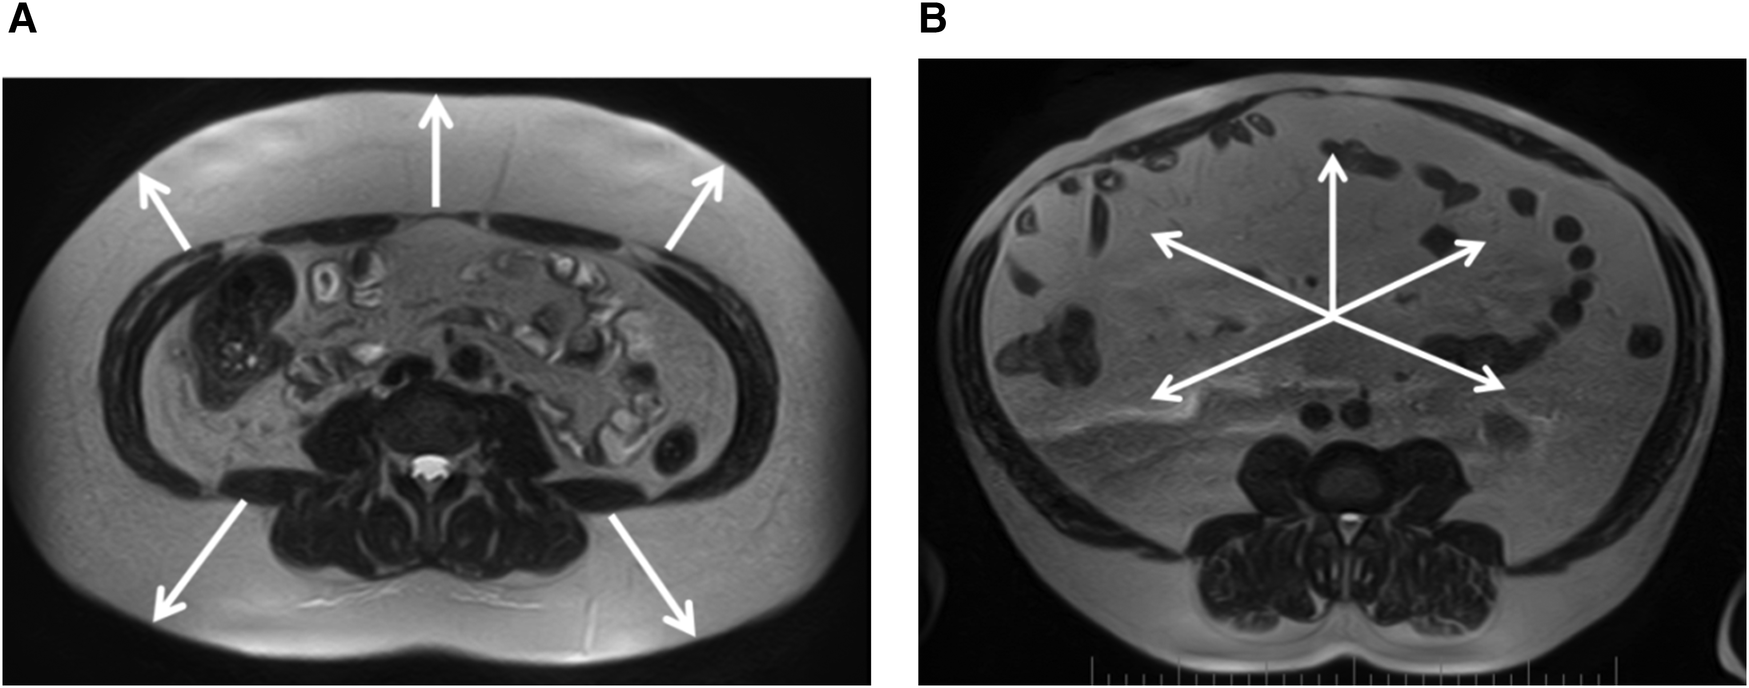

Sex differences were found in the size of subcutaneous and visceral fat depots in the regions studied. In women, subcutaneous fat was more pronounced (Figure 2A), whereas in contrast, men had larger visceral fat depots (Figure 2B), including PRAT thickness. However, the total visceral adipose tissue area was not significantly dependent on sex in our patients (Table 6).

Figure 2. (A) Female, 39 years old, pronounced predominance of the subcutaneous adipose tissue (white arrows), VSR = 0.33. (B) Male, 57 years old, marked predominance of visceral adipose tissue (white arrows), VSR = 2.21. Magnetic resonance imaging of abdominal adipose tissue/abdominal fat. Axial T2-weighted turbo spin echo images at 4-5 lumbar vertebrae levels.

During 12 months follow-up, the adipose tissue parameters studied remained unchanged in men, while a decrease in PRAT thickness was observed in women. The anthropometric parameters did not change in both groups (Table 7).